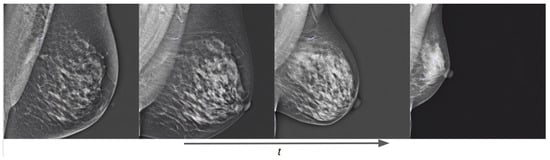

Figure 14.

Training evolution of the diffusion process on a conditional pretrained model trained with Siemens images at epochs 1, 3, 6, and 10. The prompt is: “a mammogram in CC view with high density”.

Thanks to the combined fine-tuning of the CLIP text encoder and the UNet weights, our conditional models can learn the anatomical structure and form of a mammogram, and can also push the generated image in the direction of the text prompt semantics as the training process increases.